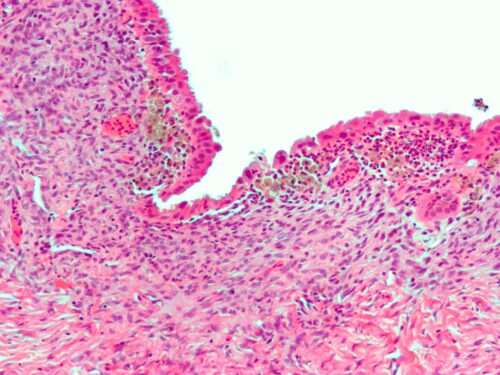

Ендоцервицит е медицински термин, с който се обозначава възпалението на лигавицата, на шийката на матката.

Етиологично, виновни са познатите на доста хора гонококови бактерии, хламидии, Streptococcus, чревни анаероби, но е напълно възможно ендоцервицит да се развие и след травматични увреди – например при разкъсване на шийката след проблемно раждане или прекарани аборти.

Той също се дели на остър и хроничен, както и първичен и вторичен.

Клиничната картина се отличава с наличие на гноен флуор, диспареуния , болка при сексуален акт, контактни кръвотечения и др. Много типично е изтичането на слуз, примесена с гной. Лечението на ендоцервицит е антибиотично, а може в добавка или при липса на ефект да се приложат и електрокоагулация и конизация.